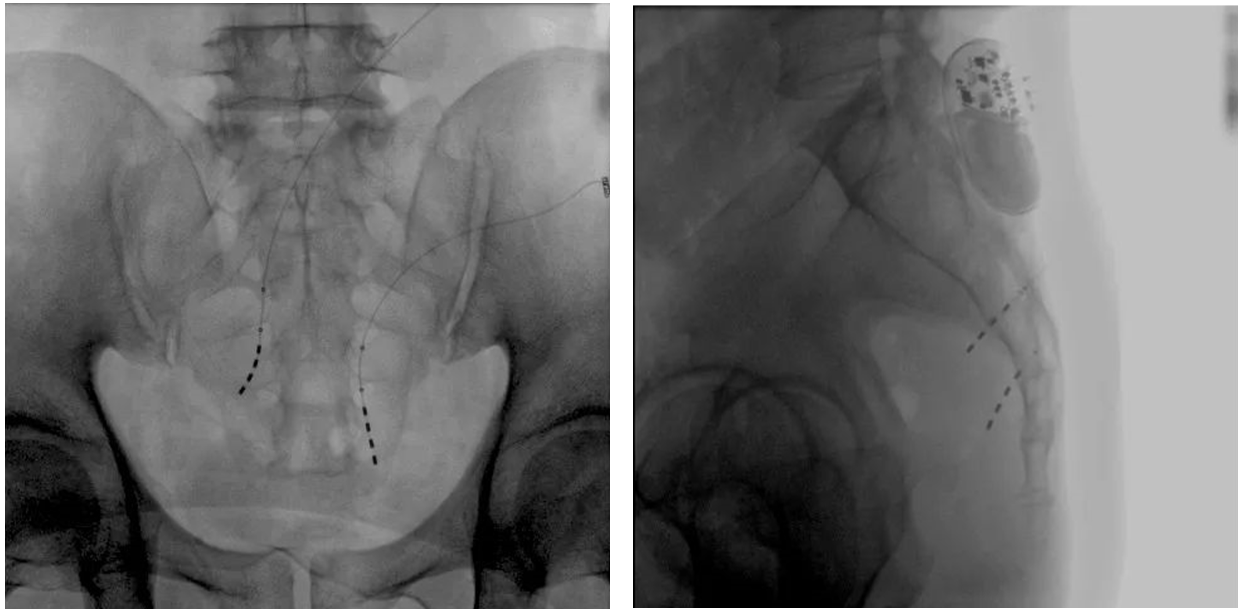

患者術(shù)前影像

大平板一體式移動(dòng)C形臂術(shù)中影像

在骶神經(jīng)調(diào)控術(shù)或者骶神經(jīng)刺激術(shù)(SNS)中,醫(yī)師首先會(huì)在透視引導(dǎo)下把電極通過(guò)導(dǎo)針插入到骶3神經(jīng)孔位置,通過(guò)脈沖電流的刺激,達(dá)到興奮神經(jīng)纖維并抑制逼尿肌收縮。在這一步,醫(yī)師會(huì)先對(duì)患者的神經(jīng)刺激反應(yīng)做測(cè)試評(píng)估,如果刺激效果明顯,說(shuō)明該方案能夠達(dá)到手術(shù)預(yù)期。接下來(lái)醫(yī)師會(huì)在附近皮下脂肪處植入一塊脈沖電流發(fā)生器并與電極相連,使該部位今后能得到長(zhǎng)期的電刺激,改善OAB癥狀。